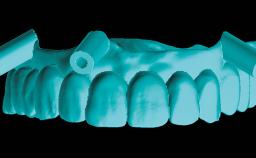

His main interests are in Computer Aided Maxillofacial and Implant Surgery, with a focus on Interdisciplinary Treatment, and in Orthognathic Surgery. He has many publications and lectures worldwide on digital tools, bone grafts, implants in the treatment of the esthetic area, complications, and the treatment of fully edentulous patients.

His main professional interests are in advanced and complex implant surgeries,

orthognathic surgery and digital technology.